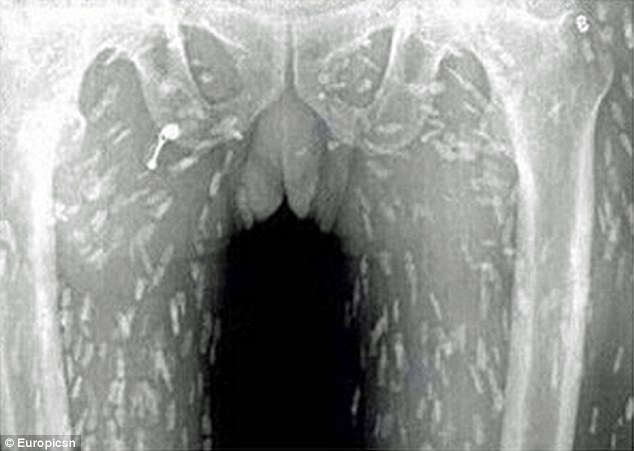

Έρευνες έχουν δείξει, ότι η κατανάλωση ωμών ή μη ψημένων ψαριών μπορεί να οδηγήσει σε ποικίλες παρασιτικές λοιμώξεις.

Η μόλυνση από κυστοειδή σκουλήκια εμφανίζεται μετά την κατάποση των προνυμφών του διφαινυλοβαθρίου, που βρίσκονται σε ψάρια γλυκού νερού όπως ο σολομός.

Η κατανάλωση μη μαγειρεμένων φαγητών που είναι μολυσμένα με αυγά κυστοειδών σκουληκιών μπορεί να οδηγήσει σε κυστικέρκωση, όταν τα ενήλικα σκουλήκια μπουν στην κυκλοφορία του αίματος ενός ανθρώπους και μπορεί να αποδειχθούν θανατηφόρα.